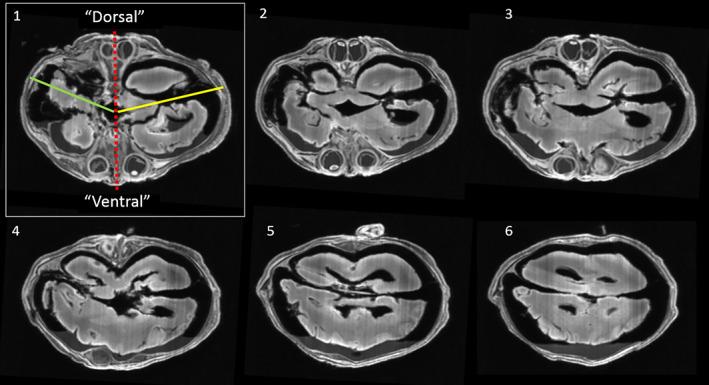

Characterizing the coalescence area of conjoined twins to elucidate congenital disorders in singletons.

Shared anomalies, always located close to the area of coalescence and observable in virtually every type of conjoined twinning, are currently seen as separate anomalies caused by mostly unknown and seemingly unrelated pathways rather than being connected to the twinning mechanism itself. Therefore, most (case) reports about conjoined twins are mere descriptions of (external) dysmorphologies lacking reflections on the possible origin of their concomitant anomalies. As we will demonstrate in this article, shared anomalies are influenced, and in some cases solely and sequentially explained, by interaction aplasia and neo-axial orientation; two embryological mechanisms to which each set of conjoined twins is subjected and are responsible for their ultimate phenotypical fate. In this review, we consider how the ventral, lateral and caudal conjunction types and their intermediates determine the phenotypic presentation of the twins, including patterns of shared malformations and anomalies, which in themselves can be indistinguishable from those encountered in singleton cases. Hence, it can be hypothesized that certain anomalies in singletons originate in a fashion similar to that in conjoined twins.

共享异常通常位于融合区域附近,几乎可以在每种联体双胞胎中观察到,目前被认为是由大多数未知且似乎无关的途径引起的单独异常,而不是与孪生机制本身有关。因此,大多数关于联体双胞胎的(病例)报告只是对(外部)畸形的描述,而没有反映其伴随异常的可能起源。正如我们将在本文中展示的那样,共享异常受到相互作用发育不全和新轴向取向的影响,在某些情况下,这两种胚胎发生机制仅单独且顺序地解释了它们,这是每一对联体双胞胎都经历的,也是它们最终表型命运的原因。在这篇综述中,我们考虑了腹侧、侧方和尾侧连接类型及其中间型如何决定双胞胎的表型表现,包括共享畸形和异常的模式,这些模式本身与单胎病例中遇到的模式无法区分。因此,可以假设某些单胎中的异常是类似于联体双胞胎中的异常起源的。